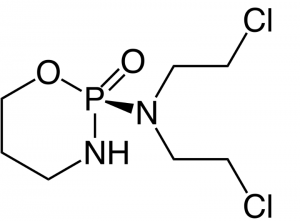

Il existe par ailleurs une synergie d’action entre le microbiote et certains médicaments utilisés dans le traitement des cancers. Le cyclophosphamide par exemple – une chimiothérapie couramment utilisée en oncologie – augmente la perméabilité intestinale : cela permet à certaines bactéries d’atteindre l’immunité systémique et de provoquer une réponse immune dont certains médiateurs ont aussi des propriétés anticancéreuses.

Il existe par ailleurs une synergie d’action entre le microbiote et certains médicaments utilisés dans le traitement des cancers. Le cyclophosphamide par exemple – une chimiothérapie couramment utilisée en oncologie – augmente la perméabilité intestinale : cela permet à certaines bactéries d’atteindre l’immunité systémique et de provoquer une réponse immune dont certains médiateurs ont aussi des propriétés anticancéreuses.